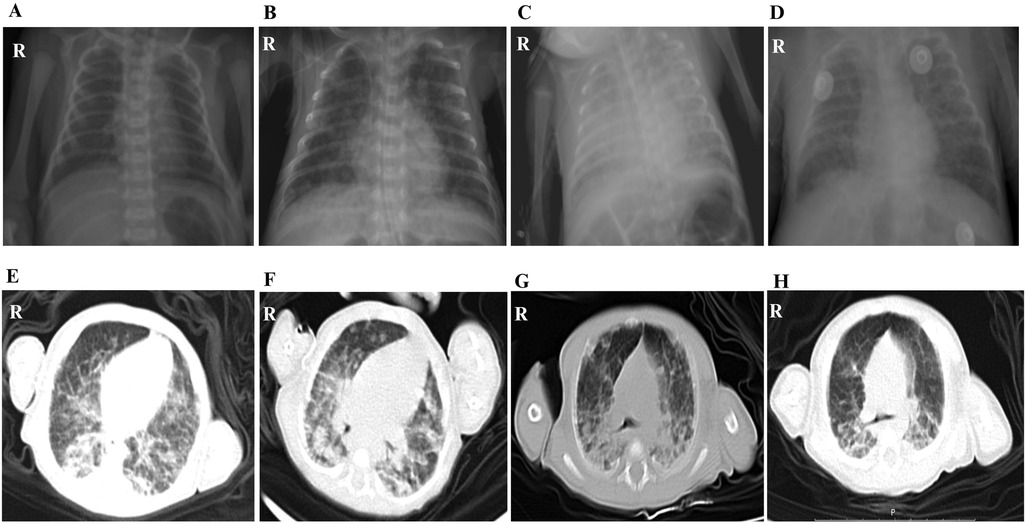

Out of the 11 cases, only one case showed scattered low-density lesions in the occipital and parietal lobes by CT. Although all infants were premature and required respiratory support postnatally, the radiographic imaging before broad-spectrum antibiotics and subsequent response to anti-TB therapy helped distinguish tuberculous lesions from changes related to RDS or BPD. Microbiological confirmation further supported the diagnosis of CTB. Moreover, alterations in lung imaging of a very preterm baby, who was 27+5 weeks old at birth, at the time of CTB diagnosis and on the 70th day posttreatment, verified that the child's chest x-ray images at the time of diagnosis showed no obvious signs of primary syndrome or miliary TB. Following standardized anti-TB treatment, the child’s clinical symptoms gradually improved, but the changes in lung imaging still did not improve significantly, and only on the 70th day following anti-TB treatment, lung imaging exhibited the onset of lesion absorption (Figure 3).

Figure 3

Chest imaging of a patient: Panels A, B, C, and D show chest X-rays at different instances, highlighting variations in lung appearance. Panels E, F, G, and H display CT scans capturing cross-sectional views of the lungs, revealing patterns and structures within the chest cavity. Each image is labeled with an \

Figure 3. The lung imaging changes of a very premature child of 27+5 weeks from birth to diagnosis of CTB to 70 days after treatment. (A) Chest radiograph at birth. (B) Chest radiograph of CTB was confirmed on the 29th day after birth. (C) Chest radiograph on the 38th day after birth, the 9th day after anti-TB treatment. (D) Chest radiograph on the 45th day after birth, the 16th day after anti-TB treatment. (E) Chest CT scan images on the 57th day after birth, the 28th day after anti-TB treatment. (F) Chest CT scan on the 71st day after birth, the 42nd day after anti-TB treatment. (G) Chest CT scan on the 85th day after birth, the 56th day after anti-TB treatment. (H) Chest CT scan images on the 99th day after birth, the 70th day after anti-TB treatment.

As for the chest CT scan image, changes of CTB were not very specific. In this study, pulmonary imaging findings of 11 infants indicated increased lung texture, disorder and blur, patches, no typical primary syndrome, and miliary pulmonary TB. Some patients showed mediastinal lymph node enlargement, with no obvious hilar lymph node enlargement. Nevertheless, the patchy shadow also had its characteristic: the pulmonary lesions worsened gradually before diagnosis, showed no improvement after broad-spectrum antibiotic treatment, and the lesions were gradually absorbed after anti-TB treatment. There was no hepatosplenomegaly reported in this group. As reported in the cranial CT imaging of this infant revealed scattered low-density lesions in the occipital and parietal lobes. This was the only one in our cohort with documented central nervous system (CNS) lesions. His general clinical presentation was poor activity, apnea, feeding difficulties, and respiratory distress. In the context of CTB, neurological symptoms might be subtle and overlap with sepsis or prematurity-related complications, making clinical distinction challenging. No tuberculous meningitis was found in CSF culturing, and the routine examinations of CSF were negative. This was not rare in early or localized CNS TB without meningeal involvement. Isolated parenchymal tuberculomas may not shed bacilli into the CSF, especially in early stages. The absence of CSF abnormalities implied that an immature blood–brain barrier in preterm infants may facilitate bacillary entry, but the immune response may be attenuated, delaying typical CSF changes. Thus, the current case highlighted the significance of taking neuroimaging into account in infants with CTB who have persistent or inexplicable symptoms, even when their CSF is normal.